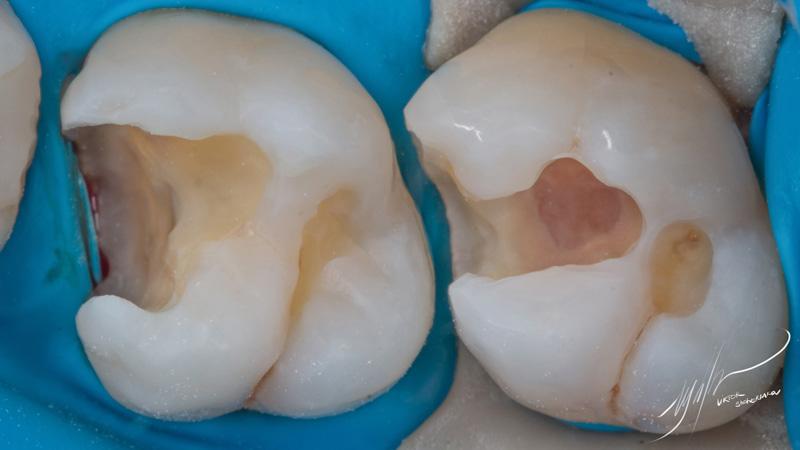

В данном клиническом случае проводилась реставрация зубов 1.6 и 1.7. Часть полостей была заполнена материалом SDR для смягчения воздействия полимеризационного стресса на композит, а также для более быстрого заполнения части внутреннего объема.

Основной оттенок для восстановления морфологических элементов – Ceram-x SphereTec A3. В качестве материала для финального моделировния был использован Filtek Ultimate White.